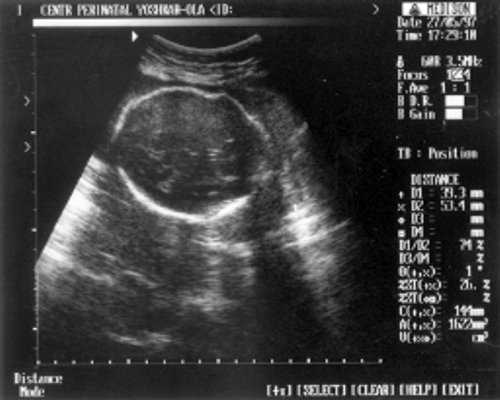

- ДБ (длина бедра) = 24 мм - 17 нед. (рис. 2)

Рис. 2. УЗИ плода - бедро.